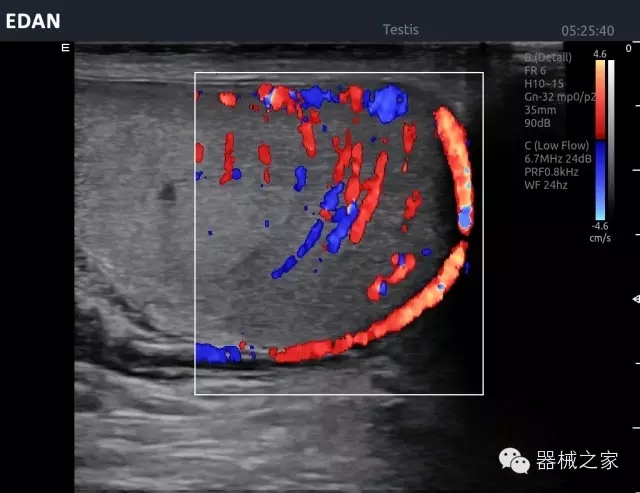

臨床圖片賞析

睪丸低速血流